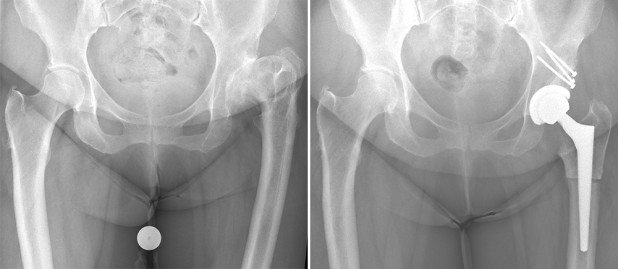

Fall 1: 74-jährige Patientin mit weit fortgeschrittener Arthrose beider Hüften

Zum Zeitpunkt der Vorstellung bei uns bestand bereits eine deutliche Einschränkung der Gehstrecke, teilweise auch nächtliches Erwachen aufgrund der Schmerzen. Die stärker schmerzende rechte Hüfte wurde über einen minimalinvasiven vorderen Zugang mit einem neuen Hüftgelenk versorgt. Aufgrund der positiven Erfahrung mit der Operation liess sich die Patientin 3 Monate später auch die Gegenseite operieren. Nach 3 Monaten war die Patientin wieder in der Lage, eine Städtereise ins Ausland mit längeren Gehstrecken beschwerdefrei zu absolvieren.

rechts: Röntgenbild 6 Wochen nach der zweiten Operation der linken Hüfte. Alle Komponenten wurden zementfrei im Knochen verankert